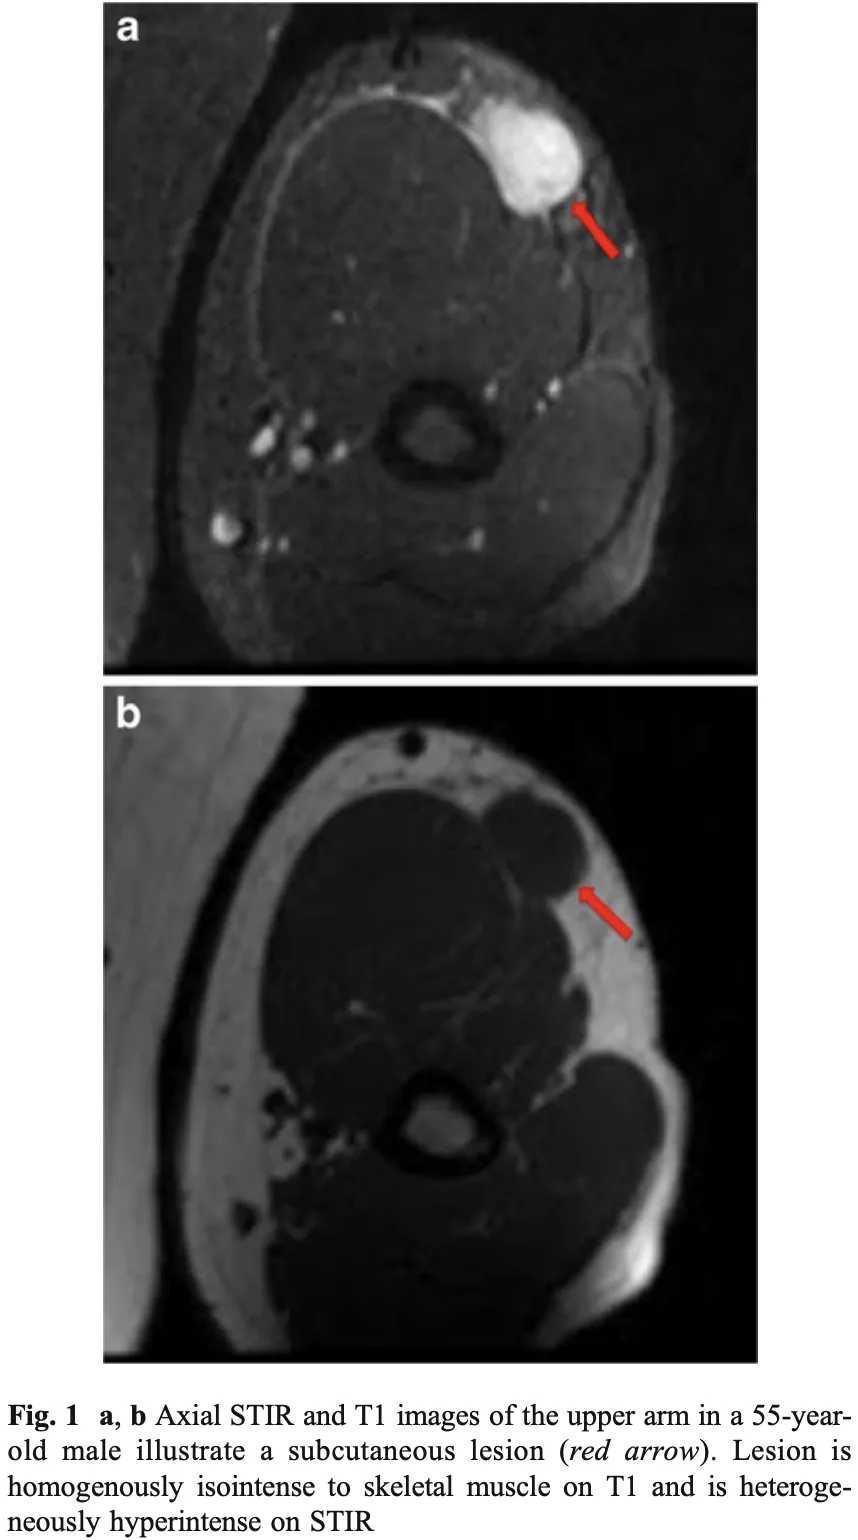

結節性筋膜炎の患者

先輩医師の整形外科クリニックからすねに腫瘤を生じた若年成人の患者さんが紹介されて受診.

すねの皮下脂肪の中に, 2 cmくらいのしこりを触知.

造影MRIを撮像して, 診断することにしました.

皮下脂肪の深部に丸い腫瘤を認めます.

造影MRIの結果, すねの皮下脂肪の深部にある浅筋膜に造影効果のある2 cm弱大の腫瘍を認め, 結節性筋膜炎が強く疑われました.

『結節性筋膜炎』は, 『筋膜炎』という名前がついていますが, 良性の軟部腫瘍のひとつです.

皮下組織や筋膜から発生し, 若年成人(20~50歳代)に多い良性の線維性腫瘍様病変です.

数週間で急速に大きくなり, 痛みや圧痛を伴うことが多く, 前腕や体幹に好発します.

通常, 3 cm以下で, その後自然に小さくなり, 消失します.

悪性の軟部腫瘍と見分ける必要があるので, 厳重に経過を観察して, 3 cmを超えて大きくなる場合には, 生検を行う方針としました.